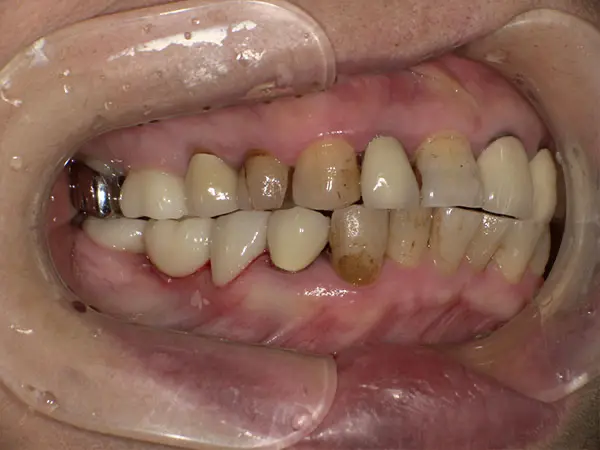

叢生・反対咬合

術前正面

術中正面

術後正面

術前上顎

| 主訴 | 歯のでこぼこ |

|---|---|

| 診断名あるいは主な症状 | 叢生、反対咬合 |

| 初診年齢 | 45歳 |

| 治療内容・装置 | マルチブラケット装置(上下表側からの矯正治療) MSE2 |

| 抜歯・非抜歯 | 下顎左第二小臼歯抜歯 |

| 治療期間 | 2年9ヶ月 |

| 費用 | 882,700円(税込) |

| 治療のリスク・副作用 | 歯の移動に伴う痛み 上下顎前歯部の歯根吸収 装置による口内炎 ブラッシング不良によるむし歯、歯周炎 |